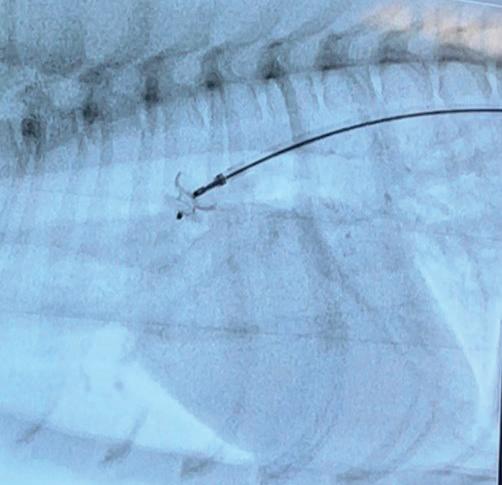

Interventional Radiology at Animal Referral Hospital (ARH) Homebush

ARH Homebush’s Internal Medicine Specialist, Dr Tim Hugo BVSc (Hons 1) FANZCVS (Small Animal Medicine) recently undertook specialised training in cardiac interventional radiology procedures in the USA led by renowned professor of cardiology at Colorado State University Dr. Brian Scansen. Focused on treating common congenital heart diseases such as patent ductus arteriosus and pulmonic stenosis, the training emphasised catheter-based treatments. Interventional Radiology offers new possibilities for conditions previously treated with open surgery, resulting in reduced patient morbidity and shorter hospital stays. ARH Homebush provides various interventional radiology treatments, including stenting and coiling for intrahepatic portosystemic shunts.